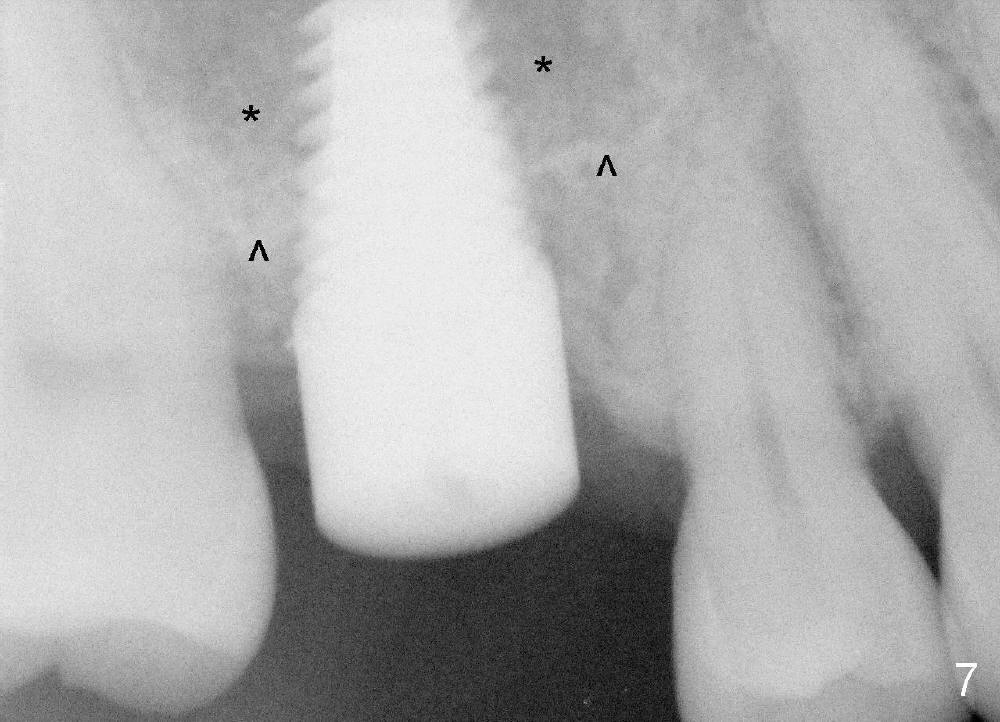

Our experience demonstrates higher failure rate associated with shorter implant in this situation. The depth of the osteotomy is then increased to 14 mm using the same series of osteotomes and taps. The bone at the top of the osteotomy finally wears off when the last tap is applied (7x17 mm). But the sinus membrane is intact. Osteogen is pushed into the osteotomy before placing a 7x14 mm implant with insertion torque > 60 Ncm (Fig.5). The implant contacts the gingiva tightly; no suture is necessary. There is no intra- or postop nasal hemorrhage. The wound heals 8 days postop (Fig.6). There is bone surrounding the apical portion of the implant in the sinus (Fig.7,8 *) 3.5 months postop. The implant is stable. There appears no crestal bone resorption 7.5 months post cementation (Fig.9 ^). Sinus lift is visible 16 months post cementation (Fig.10 (trimmed panoramic X-ray) arrowheads). There is discomfort between #2 and 3, probably due to poor oral hygiene. There is no deep pocket or bone loss (Fig.11, 26 months post cementation).